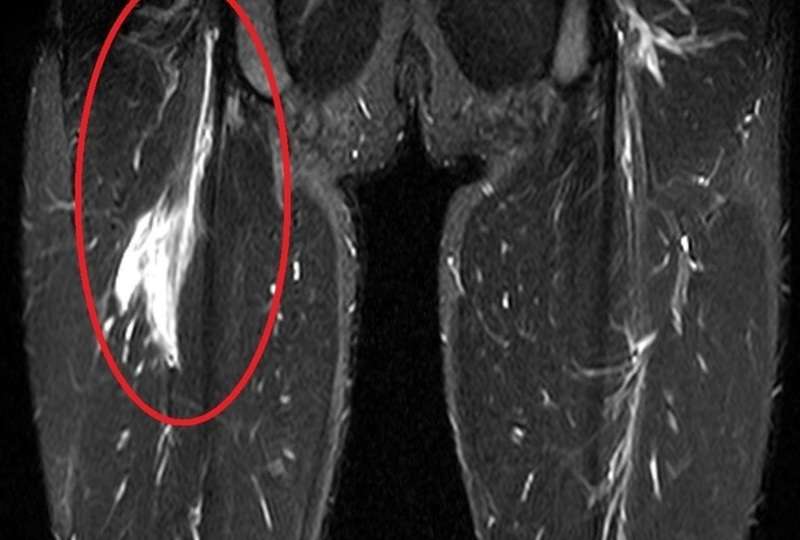

【MRI画像】

赤い丸で囲んである部分の筋肉が損傷し、出血が確認できる(広範囲に白い)